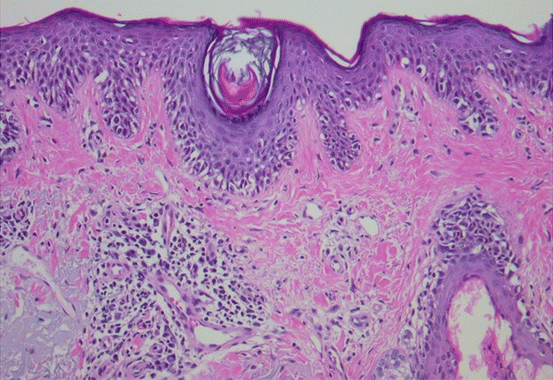

Fig. 17.2

Melanoma in situ of the lentigo maligna type: confluent proliferation of atypical melanocytes with pagetoid spread and follicular involvement and dermal solar elastosis (H&E, 20×)